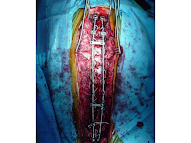

- Severa: más de 50° de desviación. Puede estar afectando o afectar algún órgano el paso a seguir sería la cirugía y necesitaría apoyo interdisciplinario, es decir, que varios especialistas apoyen antes, durante y después de la cirugía).